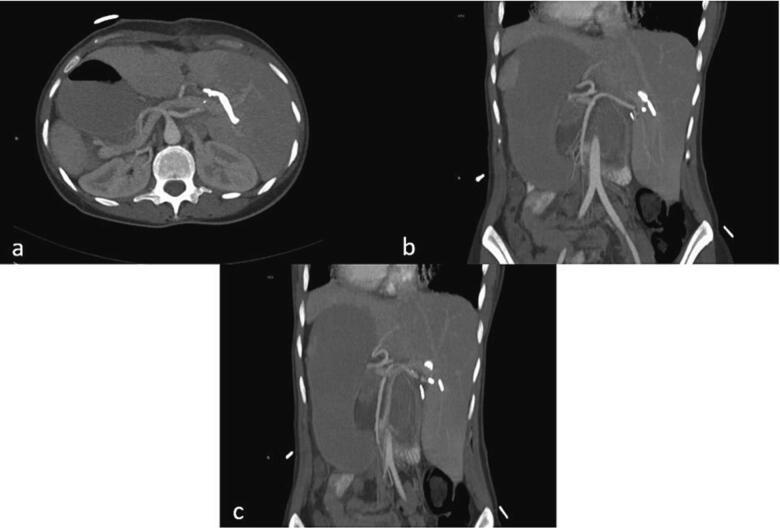

一名41岁的女性患者,已知患有卡塔格内综合征,因急性胆囊炎接受了腹腔镜胆囊切除术,并于术后第一天出院回家。然而,术后第五天,该患者因腹痛、发热和黄疸前往急诊室就诊。实验室检查显示白细胞增多和高胆红素血症。影像学检查显示CBD完全闭塞。选择了延迟治疗方法,在初次手术后六周进行了肝空肠吻合术。

腹腔镜胆囊切除术是胆囊疾病的标准手术方法。SIT独特的解剖结构增加了腹腔镜胆囊切除术期间CBD损伤的风险。外科医生需要进行镜像操作,并在SIT患者中遵循安全腹腔镜胆囊切除术的基本原则。这是SIT患者中第二例报告的CBD损伤病例。